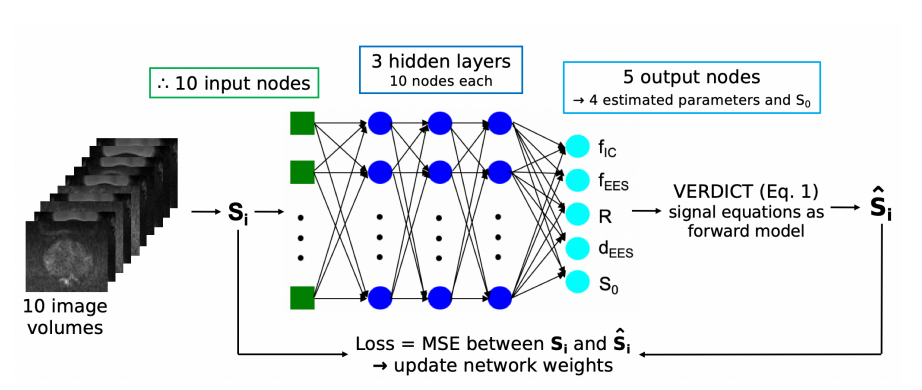

Demonstrating and assessing self-supervised machine learning fitting of the VERDICT (Vascular, Extracellular and Restricted DIffusion for Cytometry in Tumours) model for prostate.

Snigdha Sen, Saurabh Singh, Hayley Pye, Caroline M. Moore, Hayley Whitaker, Shonit Punwani, David Atkinson, Eleftheria Panagiotaki1, and Paddy J.Slator